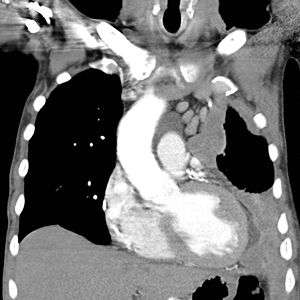

Left-sided mesothelioma (seen on the right of the picture): chest CT